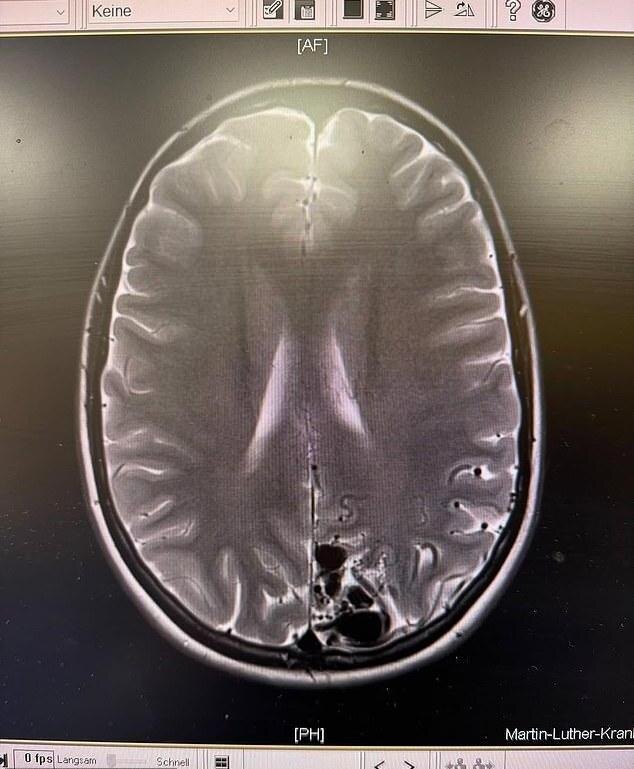

🧠 Артериовенозная мальформация (АВМ) — врожденная патология, при которой сосуды мозга образуют опасные сплетения, минуя капилляры. Это нарушает кровообращение и может вызывать кровоизлияния, судороги и другие тяжелые осложнения. По статистике, такой диагноз встречается лишь у одного человека из 100 000.